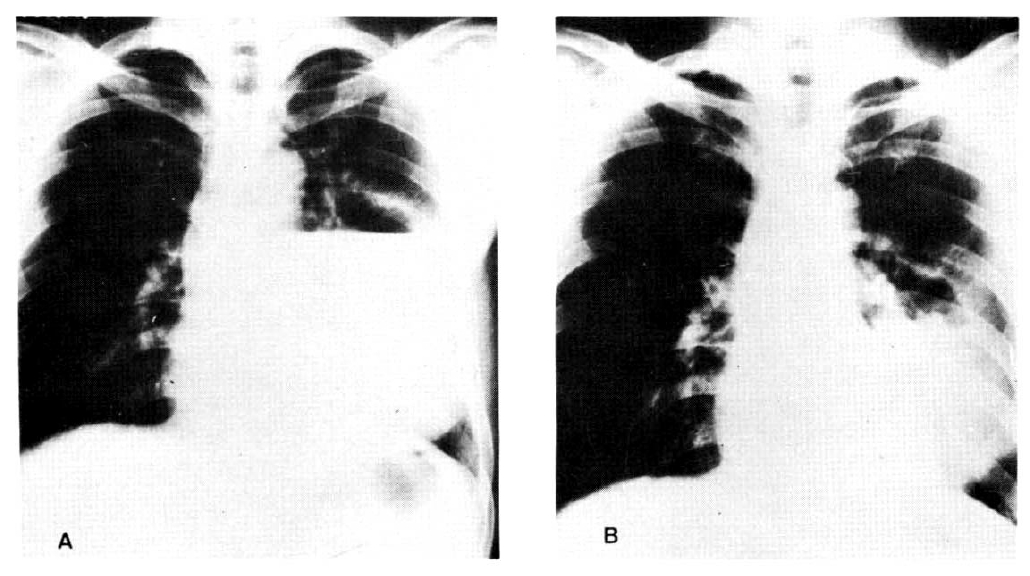

Fig. 1. and 2. are the X-rays of two cases which showed great success.

Fig. 2.

(Patient No. 4): (A) A large cystic cavity is seen in the superior segment of the left lower lobe. (B) Note the remarkable radiological improvement after transbronchial catheter drainage via a fiberoptic bronchoscope in the X-ray taken 6 hours later.